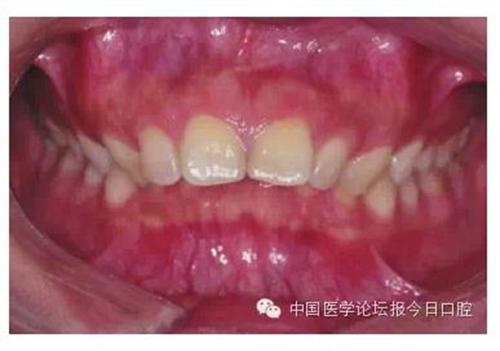

由于有很多患者在微笑時“頰廊”會比較明顯(圖2),這種情況往往預示著其上牙弓狹窄或上頜后牙過于舌傾(圖3),從而影響了微笑的美觀,正畸時有必要直立上頜后牙,這樣就可以創(chuàng)造飽滿的微笑,這類病例可以考慮選擇上頜前磨牙的零度轉矩,有效實現(xiàn)上頜后牙的直立。

圖2 患者在微笑時“頰廊”

圖3 存在“頰廊”者的口內情況